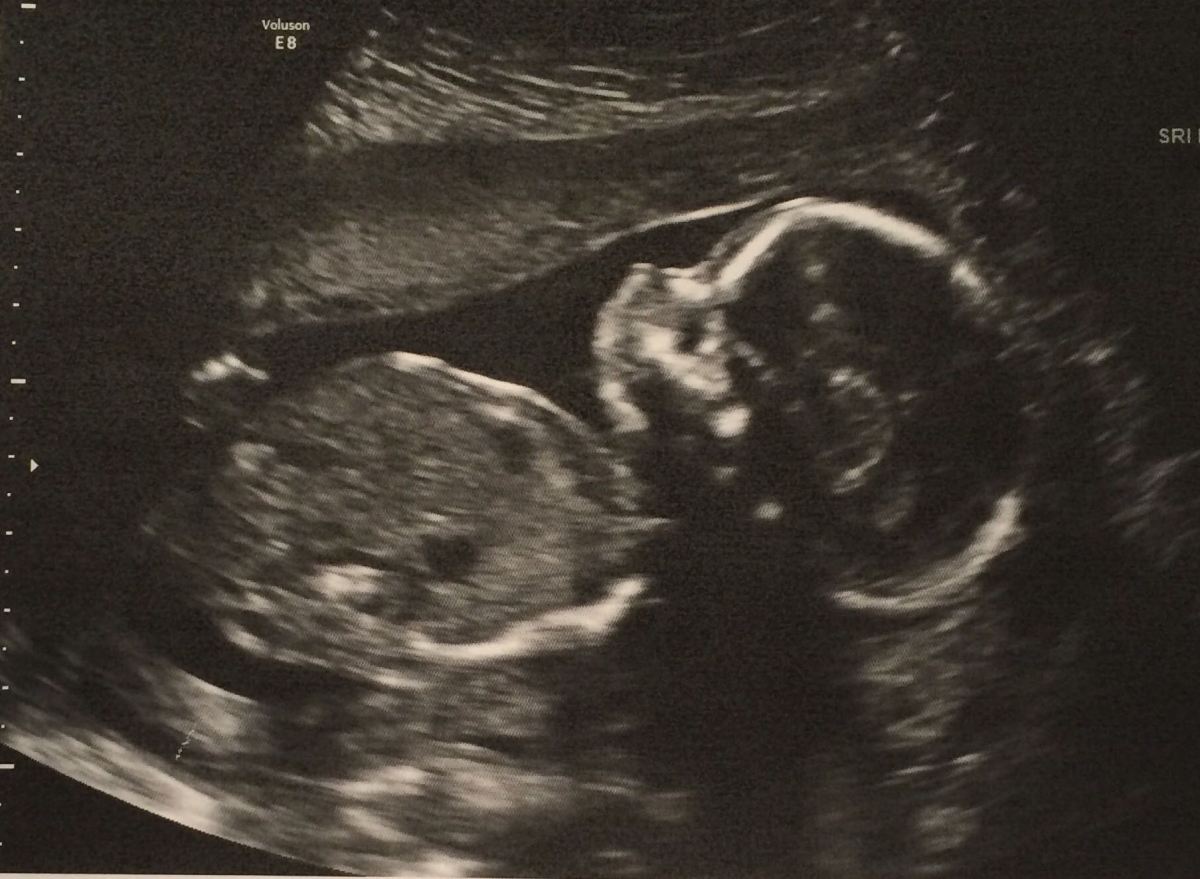

Dalla stampa si è appreso che a New York da oggi si può abortire fino al nono mese. Qualcuno, non sapendo minimamente di cosa...